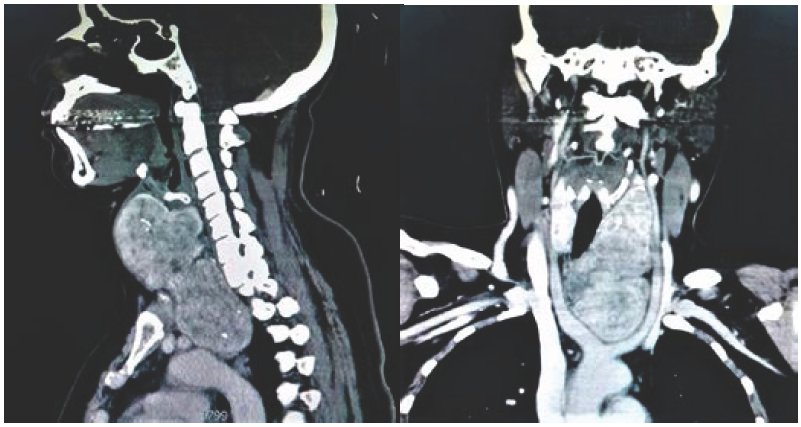

PRESENTACIÓN DEL CASO

Masculino de 45 años de edad, con hipertensión arterial como único antecedente relevante. Presentó disfagia alta, disfonía y disnea leve, de aproximadamente 6 meses de evolución, de inicio insidioso y empeoramiento progresivo, por lo que acudió a consulta. A la exploración física destacó aumento de volumen en cara anterior del cuello, de consistencia blanda y de gran tamaño, adherido a planos profundos, así como signo de Pemberton positivo (sugiriendo síndrome de vena cava superior). Se solicitó ultrasonido de cuello a la brevedad, detectándose bocio, eventualmente realizándose además tomografía de cuello y tórax donde se corroboró el diagnóstico de bocio con extensión intratorácica a mediastino superior, complicado con compresión faríngea, esofágica, laríngea, traqueal y de arterias y venas cérvico-mediastínicas. Contó con perfil tiroideo normal. Fué referido a tercer nivel de atención médica, donde se decidió su resección quirúrgica (tiroidectomía total con resección de la sección mediastínica), con mejoría clínica considerable. Se reportó bocio multinodular en estudio histopatológico.

La prevalencia en Estados Unidos es del 0.02 - 0.5%1. Su principal variedad histológica es el bocio multinodular3. Hasta 8% son malignos2. El tipo cérvico-mediastínico es el más común (como el caso que se muestra). Tiene predominio femenino (de 3:1 a 5:1.3), surgiendo generalmente después de los 20 años de edad, siendo más frecuente entre la cuarta y quinta décadas de la vida3. El 70 - 80% son sintomáticos (masa cervical, disnea, estridor, disfagia, disfonía, hemorragia digestiva por várices esofágicas, síndrome de vena cava superior, ataques isquémicos transitorios y edema cerebral).1